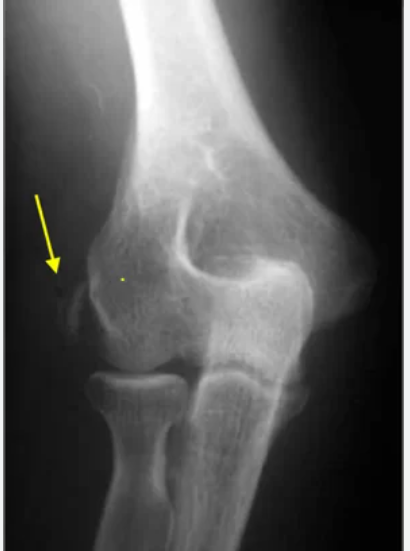

Quais achados podem ser vistos em uma radiografia de um cotovelo com epicondilite lateral ?

Calcificações, porém rx é de pouco auxilio nessa patologia